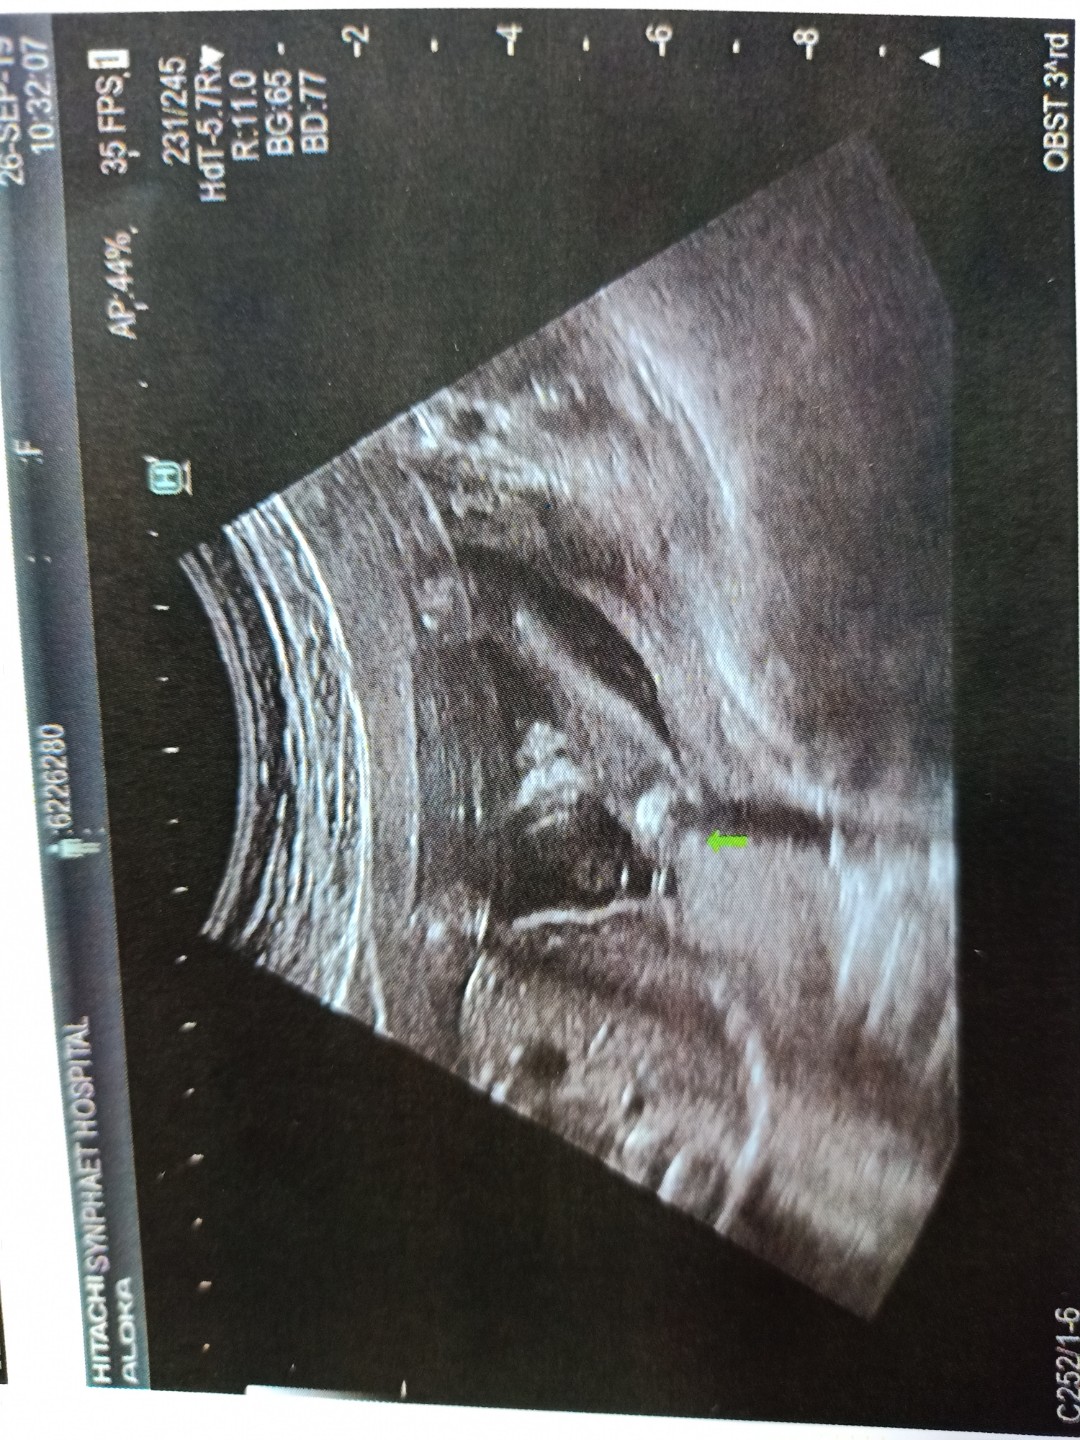

ในใบซาวด์25วีค5วันค่ะ